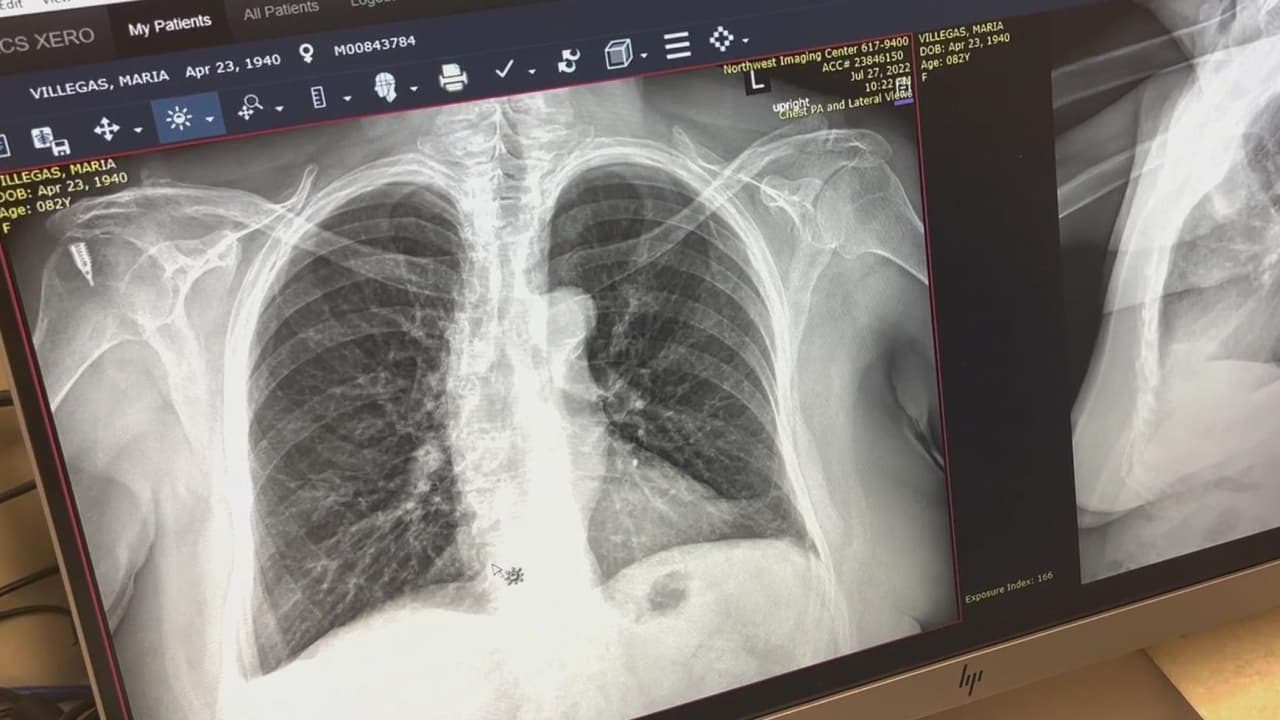

La importancia de la detección temprana para luchar contra el cáncer de pulmón

El cáncer de pulmón presenta una de las tasas más altas de muerte